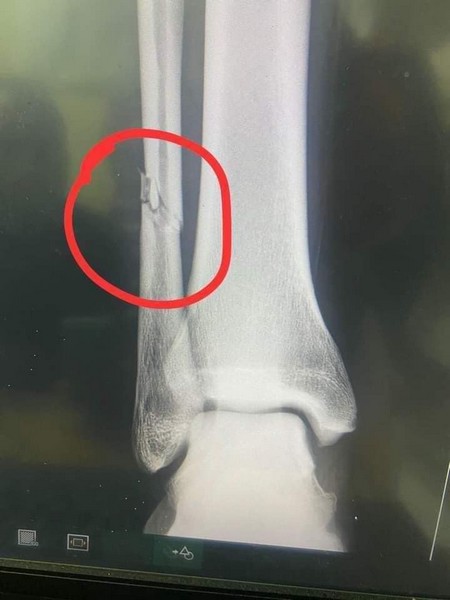

14-03-2022 11:54 - Fracture du péroné pour Adama ba

Rimsport - Après avoir subi un tacle violent d'undéfenseur de Simba Sc, dimanche (13 mars) en match comptant pour la quatrième journée de la Coupe de la Confédération - CAF, Adama Ba a révélé sur les réseaux sociaux souffrir d'une fracture du péroné de la jambe droite.

Un tacle extrêmement violent au tibia du joueur tanzanien, et Adama Ba qui crie de douleur. Les images font froid dans le dos. L'attaquant mauritanien de RS Berkane, revenu au meilleur de sa forme, après sa retraite internationale a été sévèrement blessé.

Sa période d'indisponibilité pourrait dépasser un mois. La défaite des marocains (0-1), en déplacement est forcément passée au second plan après cette grave.